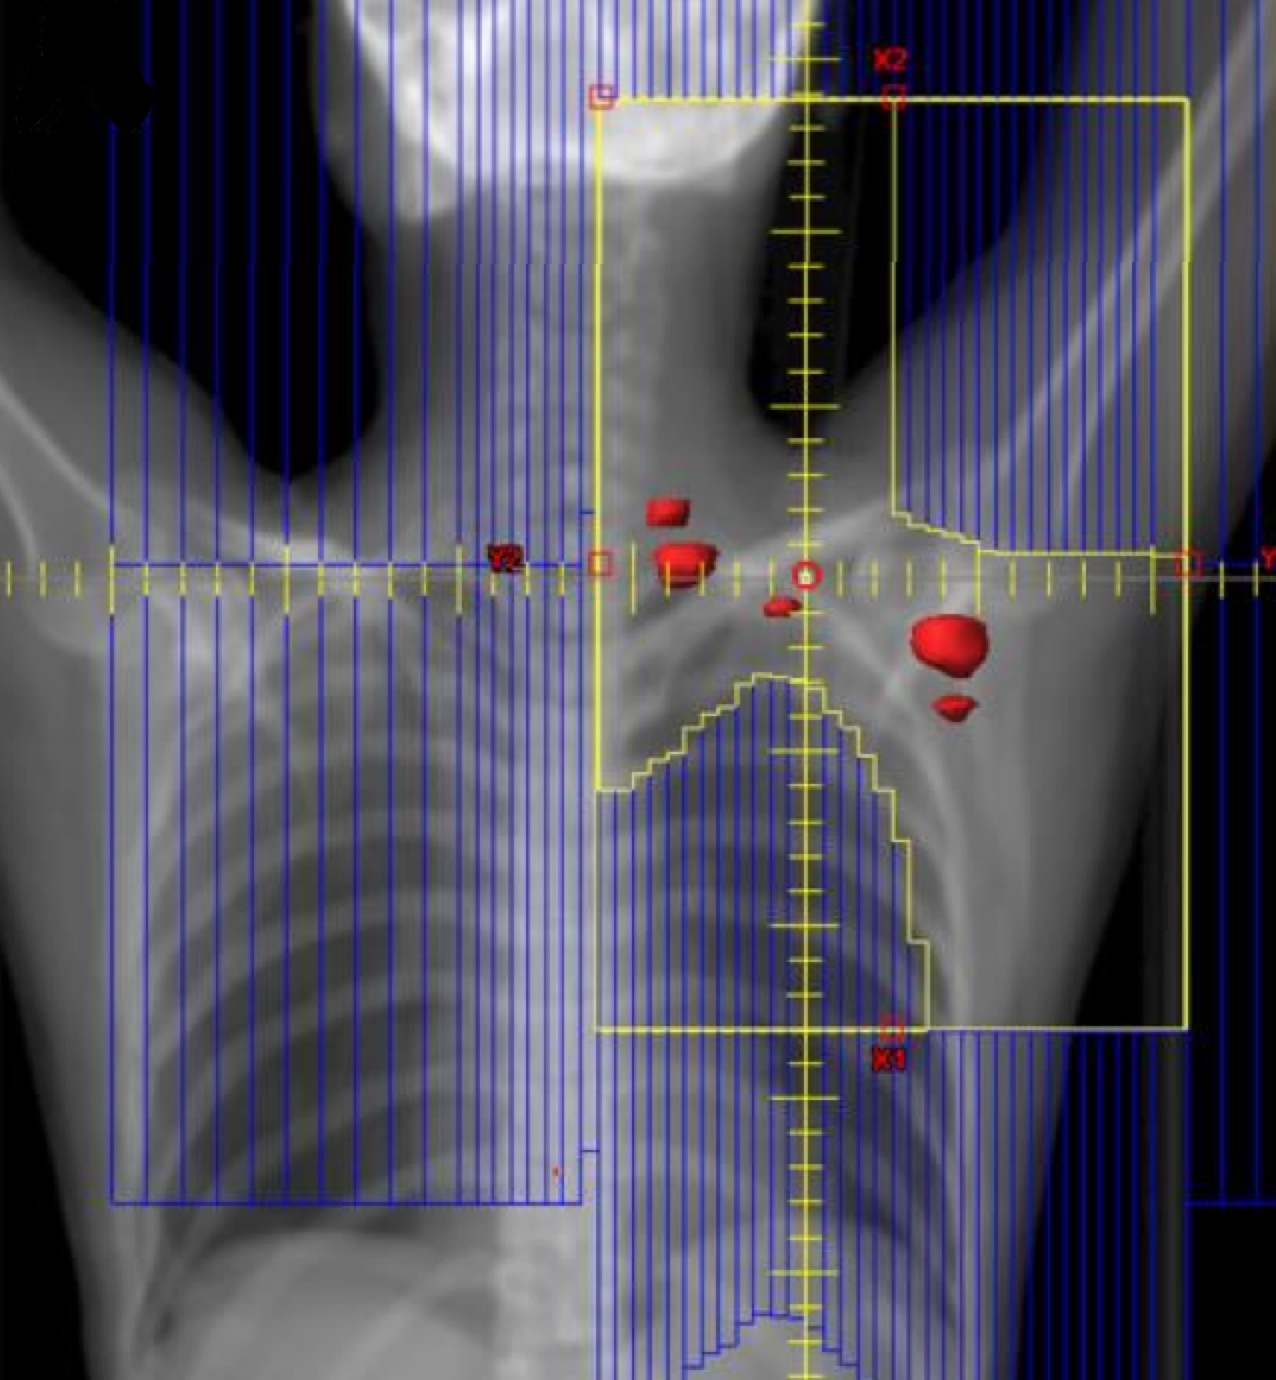

ISRT is most commonly recommended now as the most appropriate treatment field (Yaholom). Determining the optimum involved site definition may require incorporation of PET and MRI as well as pre-treatment and treatment planning CT to define the optimum volume.

Involved Site Radiation Field

• includes original extent of disease with margins to account for imaging limitations and disease specifics

• Recommended, based on GTV → CTV → PTV

• CTV=pre-chemotherapy extent of disease based on PET-CT

• CTV adjusted to exclude uninvolved normal tissues such as lung after tumor shrinkage

• CTV expanded to incorporate imaging/disease uncertainties

ISRT targets the site of the originally involved lymph nodes. This volume encompasses the pre-chemotherapy/pre-operative volumes. The fields are modified to spare adjacent uninvolved organs (lungs, bone, muscle, kidney), when the disease shrinks following chemotherapy. Concerns about the precise accuracy and localization of pre-treatment disease may lead to an expansion of the CTV based on clinical judgement. For NLPHL where radiotherapy is the sole modality treatment, a larger field should be considered.